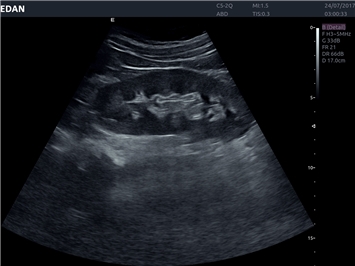

EDAN Acclarix LX4 представляет собой инновационную ультразвуковую систему, построенную на усовершенствованной платформе Acclarix. Сочетание высокого качества визуализации с интеллектуальным рабочим процессом делает эту систему оптимальным выбором для клиник, ценящих эффективность и экономичность.

• 3D/4D-визуализация с автоматическим редактированием объема (eFace)

• Общей визуализации

• Акушерства и гинекологии